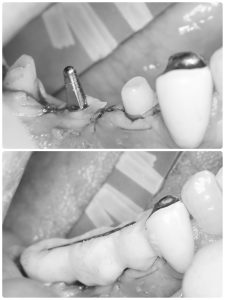

本日は右下オペ

今回は暫間インプラントも併用し、バッチリ💪

ドリリングはフリーハンド

CT精査し3D画像にて方向を入念に頭に入れてれば